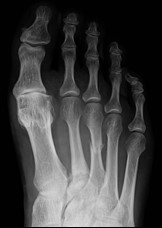

Które badanie zostało zarejestrowane na przedstawionym radiogramie?

Ilustracja do pytania 21

A. Jamy brzusznej wykonane poziomą wiązką promieniowania.

B. Płuc wykonane metodą Przybylskiego.

C. Układu moczowego z użyciem środka kontrastującego.

D. Dróg żółciowych metodą cholangiografii śródoperacyjnej.